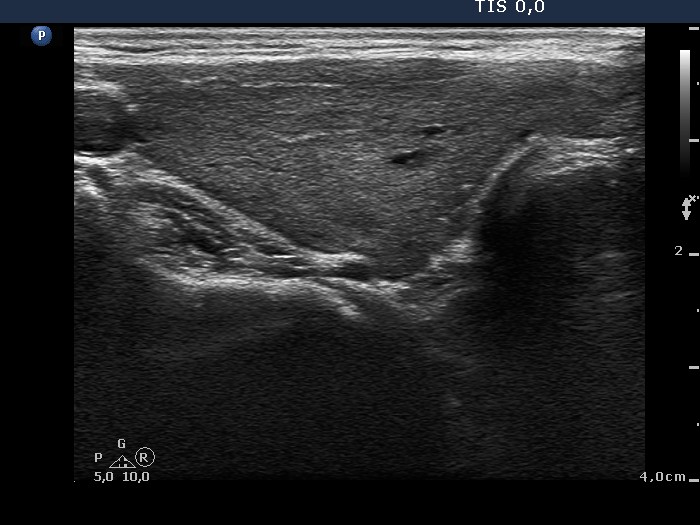

Clinical data: A 31-year-old woman was referred for evaluation of a suspicious nodule. She was treated for Graves' hyperthyroidism for 15 months. At the time of the discontinuation of the thyrostatic therapy, an ultrasound examination was performed, and a hypoechogenic nodule with microcalcifications was described.

Ultrasonography: The thyroid was minimally-moderately hypoechogenic with several insignificant discrete areas. There were two hypoechogenic small lesions close to each other within the left lobe. The larger one displayed hyperechogenic lines and figures in the back wall of cystic areas; these are optical artifacts caused by posterior back wall enhancement.

Cytology was performed from the hypoechogenic lesion in the left lobe and resulted in benign lesion with hormonal influences.

Comment. The optical artifacts caused by posterior back wall enhancement should not be interpreted as microcalcifications.